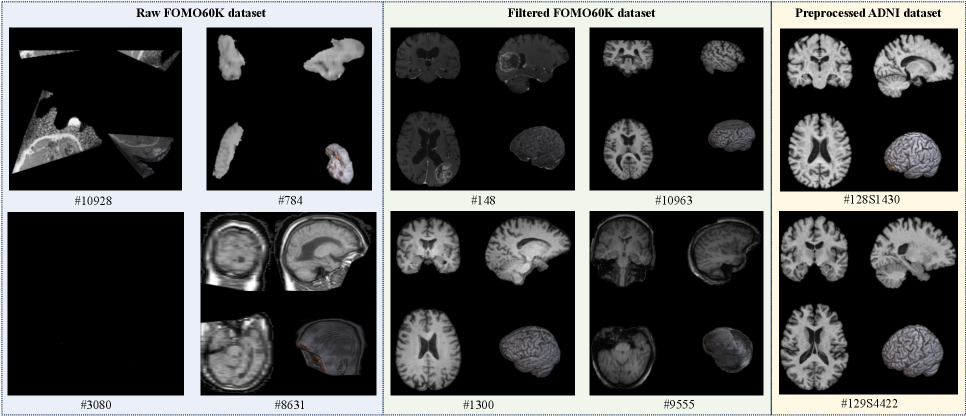

Refer to caption

Fig. 2: Several representative brain MRI samples intentionally selected to reflect quality differences across the three pretraining datasets used in this study; each sample is labeled with its original data index for reference and review.

In the pretraining stage, we trained MAE on three different unlabeled MRI datasets, some samples illustrated in Fig.2:

• Raw FOMO dataset: The FOMO dataset is a large-scale and heterogeneous brain MRI dataset, where the scans of 13,900 sessions and 11,187 subjects, aggregated from 16 publicly available sources. FOMO exhibits a wide range of image resolutions and contrasts. Based on this dataset, we collected all FOMO T1 MRI 8017 scans for pretraining. Notably, a considerable portion of the brain scans show evident heterogeneity and artifacts, such as spatial distortion, missing tissues, and non-standard orientations.

• Filtered FOMO dataset: This subset includes 3511 scans, which was obtained by removing scans with severe artifacts or imaging failures according to imaging quality and resolution criteria based on the raw FOMO dataset. The majority filtered MRI scans exhibit spatial dimensions no smaller than 204×240×150.

• Preprocessed ADNI dataset: An additional set of 319 MRI and 398 PET scans was collected from the same preprocessing pipeline as the ADNI downstream tasks but without subject overlap among the 1,115 individuals used in the fine-tuning age prediction stage.